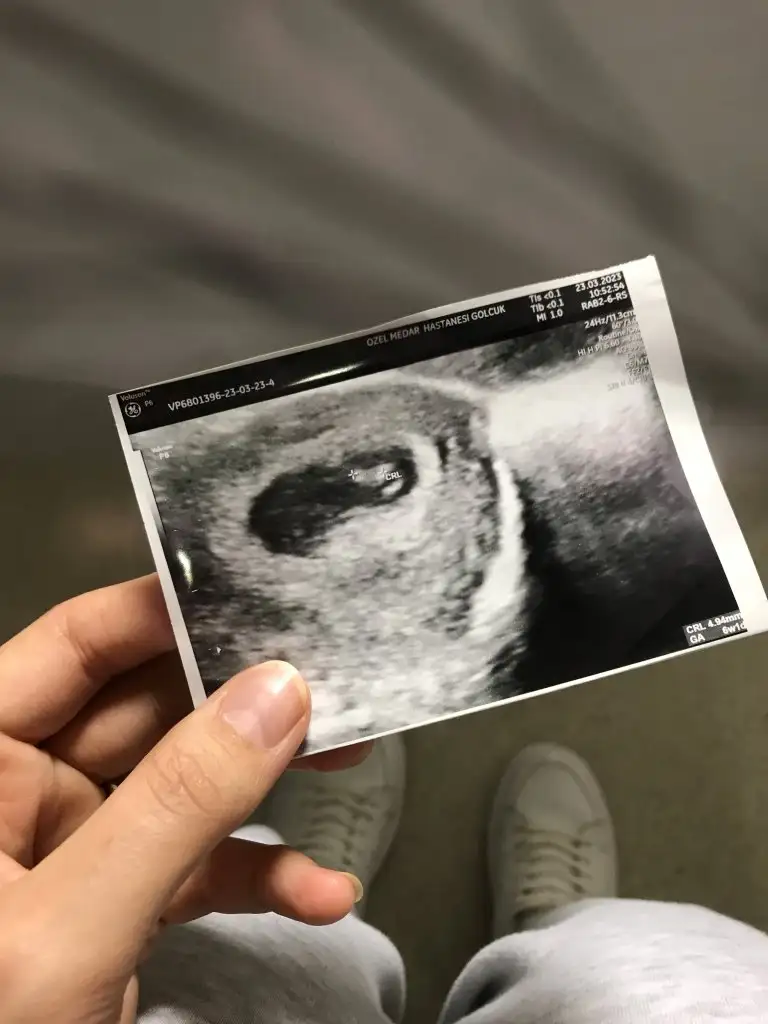

Kızlar banada yorum yapar mısınız 6 haftalık görüntüsü karından

Eklentiler

• 9C350551-613A-4C69-8A26-19BC49E63004.webp

53 KB · Görüntüleme: 95